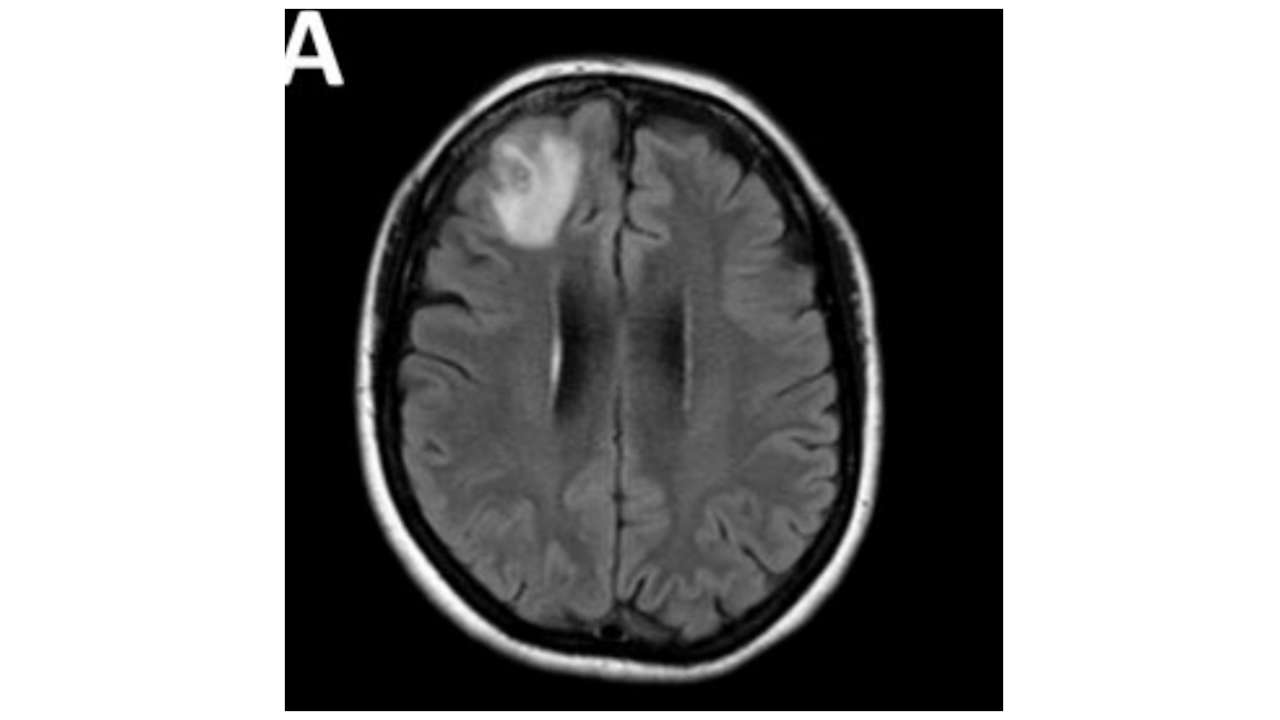

After scans showed changes in her brain, surgeon Dr Hari Priya Bandi performed a biopsy on the patient’s skull at Canberra Hospital last year and used forceps to pull out a three-inch parasite.

“This patient had been treated… for what was a mystery illness that we thought ultimately was an immunological condition because we hadn’t been able to find a parasite before and then out of nowhere, this big lump appeared in the frontal part of her brain,” Mr Senanayake said.